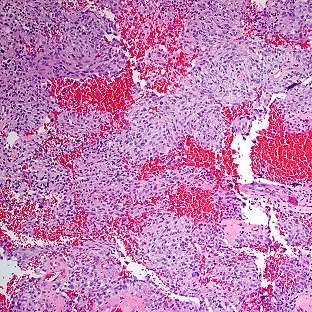

• Brain tumor cellsSurgical biopsies, which are used when imaging indicates that the tumor can be removed surgically. With a procedure called a craniotomy, the surgeon makes an opening in the skull in order to access the brain, take a sample of abnormal tissue for examination, and remove as much of the tumor as possible.

Pathology: At Wilmot, neuropathologists — pathologists who specialize in tumors of the brain and spine — will examine the tissue from a biopsy under a microscope to determine whether cancer is present.